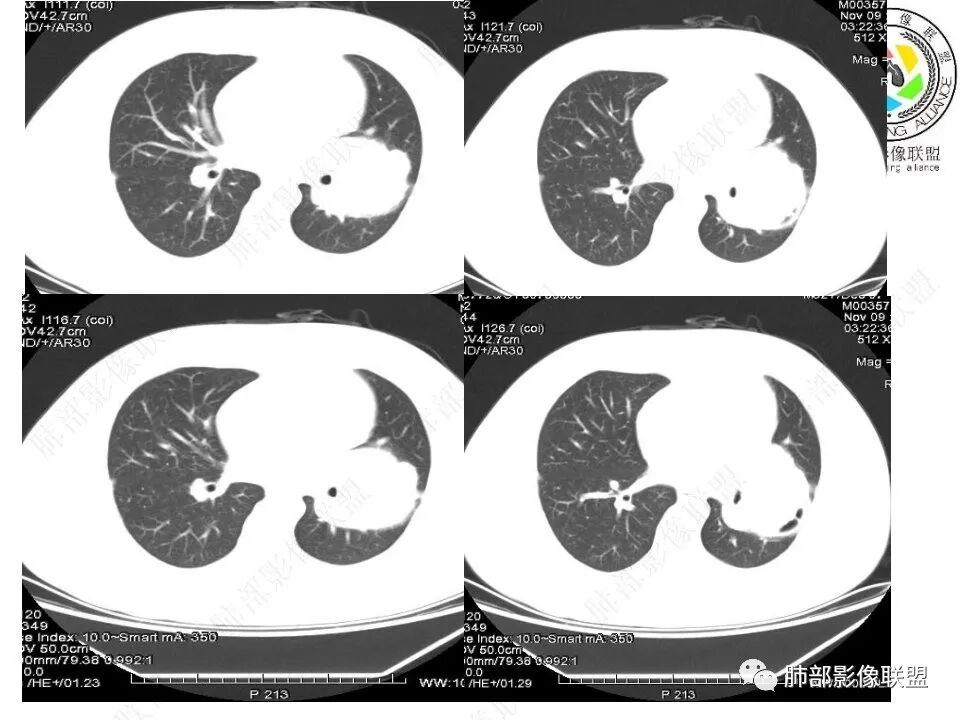

下叶基底干支气管受压下移

下叶背段支气管受压稍后内移位,通畅

就是支气管目前基本没有堵塞,只是受压

瘤肺界面清晰,支持肺外来源,支气管包绕,延迟强化,sft,psp

内部血管走行,应该不好考虑PSP

与支气管关系比较密切。无论是狭窄还是堵塞,都不好考虑SFT,如果是SFT,对支气管应该是推移,不会包绕,这种局部包绕支气管的,SFT很少见,有难度

青年男性,体检发现左肺不规则类圆形占位性病变,叶间裂区域,定位胸膜来源。左肺下叶支气管受压狭窄,但管壁光整,未见腔内阻塞或管壁受侵。包块边界清晰,浅分叶,内部密度不均匀,病灶后份见空气新月征。渐进性强化,增强动脉期见分支状血管,蛇纹血管征。肺门纵膈未见增大淋巴结,符合孤立性纤维瘤(SFT)。